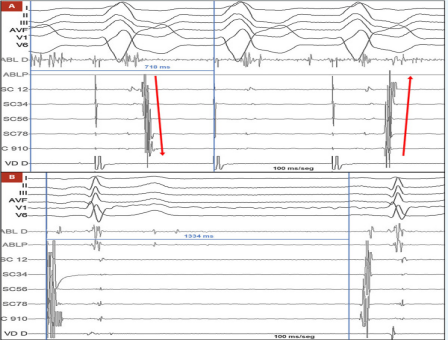

基于电生理检查结果,介入团队决定行射频消融术,而非直接置入起搏器,具体过程如下:消融路径:穿刺右侧股动脉,将消融导管(ABL)通过主动脉后入路推进至二尖瓣环(左隐匿性旁路常位于二尖瓣环附近);靶点定位:在右心室起搏期间绘制逆行心房激活图,于二尖瓣环前外侧区域发现 “融合VA间期” 及可能的通路电位,此处心房活动最早出现,确定为消融靶点;消融实施:采用功率控制射频(35W)进行消融,0.7s 后即观察到旁路传导中断,心房激活模式从 “偏心型” 转为 “同心型”(提示旁路逆传功能消失,图3A);疗效验证:消融后等待30分钟,多次尝试刺激均未再诱发出心动过速,提示消融成功;

(图3A,图3B)

窦房结功能评估:消融术中常规行窦功能测试,程序性心房刺激后窦房结恢复时间(SNRT)为1334ms(正常值 < 1500ms,图3B),表明窦房结功能正常,不存在原发性窦房结功能障碍。